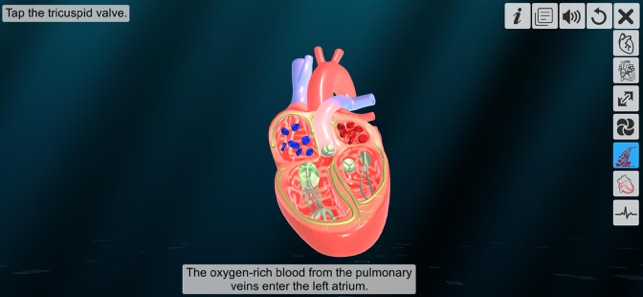

5. Blood flow of heart

‘Heart - An incredible pump’ app explains the external and internal structure of human heart through the simulation 3D model to improve the comprehension of the topic. The user can interact with the 3D model by tapping the model and getting acquainted with the particular part of the human heart. Tapping the model displays the name of the part and also the simulation module is appropriately supported with in depth information about each external and internal structure part.